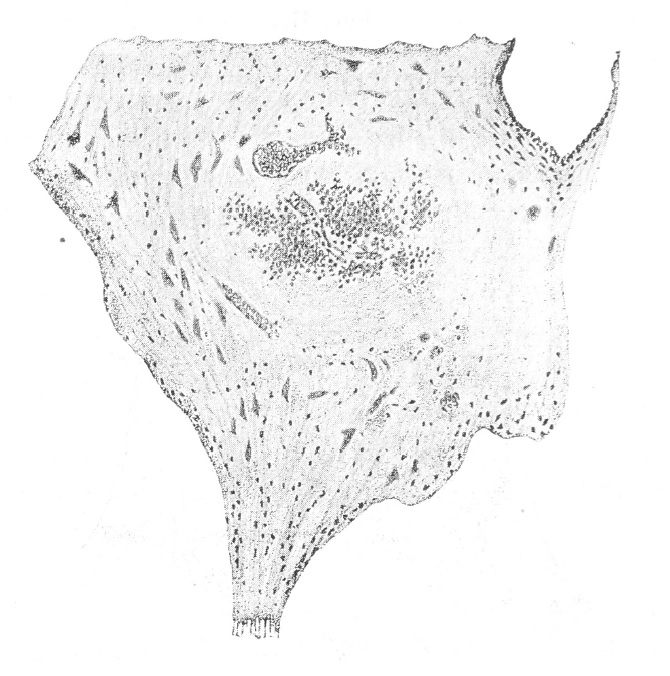

Кровоизліянія находились почти исключительно въ сѣромъ веществѣ мозга, какъ спинного, такъ и головного; лишь очень рѣдко они наблюдались въ бѣломъ веществѣ мозговой коры; въ сѣромъ воществѣ спинного мозга кровоизліянія занимали самые различные отдѣлы: они встрѣчались въ переднихъ и заднихъ рогахъ, въ боковыхъ рогахъ, причемъ располагались то въ периферическихъ, то въ центральныхъ частяхъ роговъ, то въ ихъ основаніи, то возлѣ самаго центральнаго канала; распредѣленіе кровоизліяній въ сѣромъ веществѣ не было равномѣрнымъ—у нихъ были излюбленныя мѣста, въ которыхъ они встрѣчались чаще, чѣмъ въ другихъ; кровоизліянія въ заднихъ рогахъ бывали значительно чаще, чѣмъ въ переднихъ; особенно часты были кровоизліянія въ основаніи заднихъ роговъ, гдѣ они достигали и большей величины, чѣмъ въ другихъ мѣстахъ. Наблюдавшіяся мною кровоизліянія въ сѣромъ веществѣ мозга по величинѣ ихъ можно отнести къ точечнымъ; весьма многія изъ нихъ на микроскопическомъ препаратѣ были легко замѣтны простымъ глазомъ; наибольшія по величинѣ кровоизліянія, наблюдавшіяся въ основаніи заднихъ роговъ, занимали отъ 1/3 — 1/2 разстоянія между наружной границей сѣраго вещества и центральнымъ каналомъ (рис. I).

Рис. I